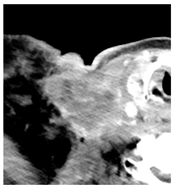

| 3 | 25–50 | 1716 | ![]() Axial CT image shows a mostly necrotic tumor in the right neck. | ![]() Axial CT image obtained 1 day after injection shows the NBTXR3 nanoparticles (arrows) in the tumor with a small amount of leakage into the surrounding soft tissues. |